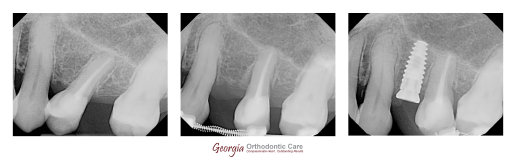

Patient missed #7 with significant spaces. Orthodontic treatment to consolidate spaces and set up ideal space for #7 before implant insertion. Photo courtesy of Dr. Lia Vo at the Vo Dentistry.